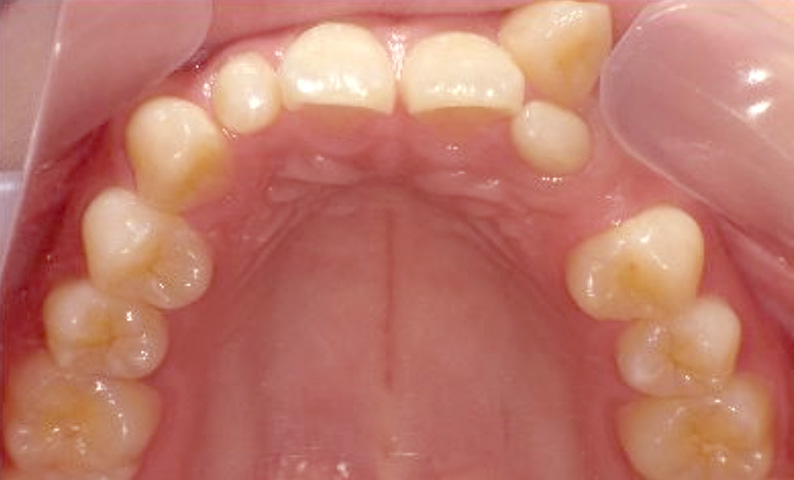

症例_025 上顎だけの部分矯正

治療期間:7ヶ月金額:30万円+税女性前歯のガタガタ上の前歯だけ

| Before | After |